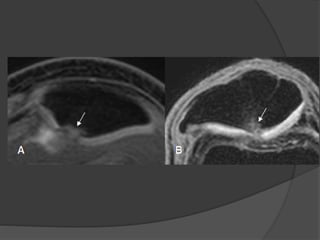

Errores de interpretación ruptura

meniscal

 Estructuras normales cuya proximidad a los

meniscos simulan roturas

 Tendón poplíteo está próximo al cuerno posterior del

menisco externo y el espacio entre ellos hiperintenso

simula una rotura meniscal